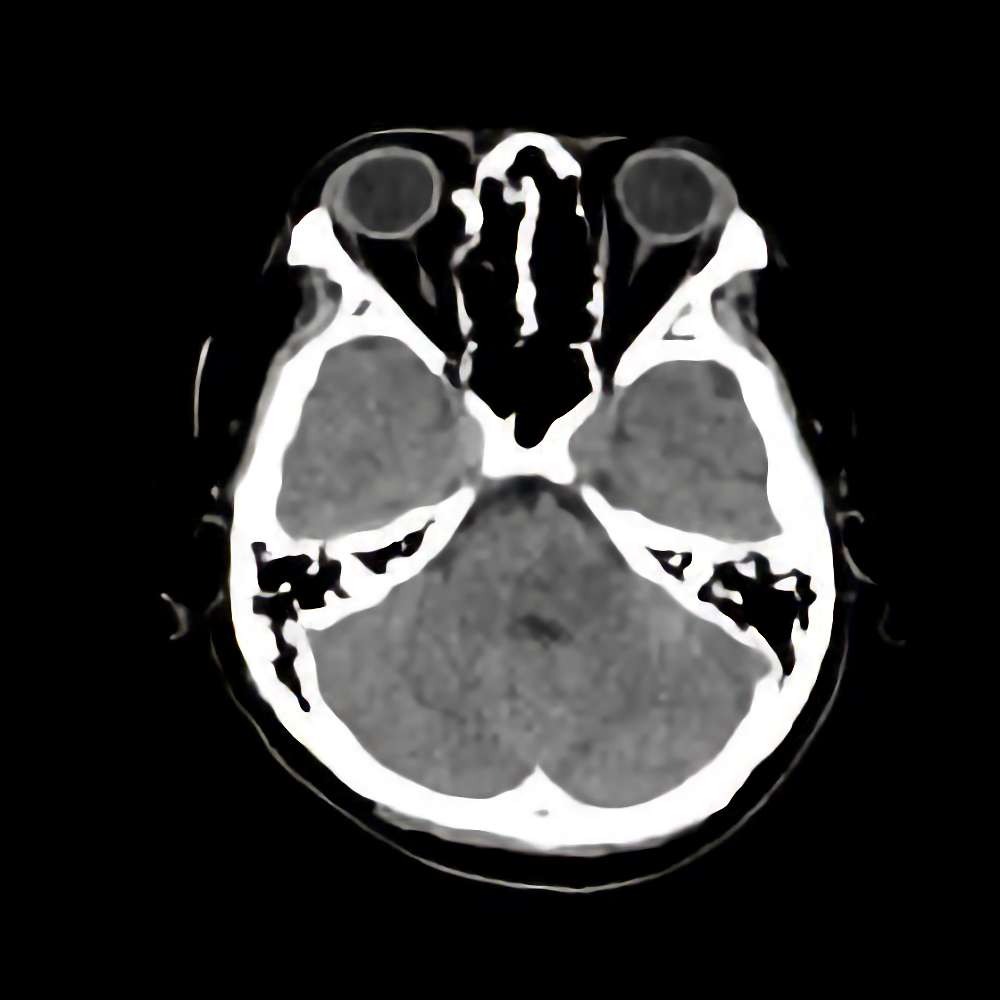

’15_102

'15年7月

10代

眼窩腫瘍

断層撮影

手術前

1

手術前2

手術後